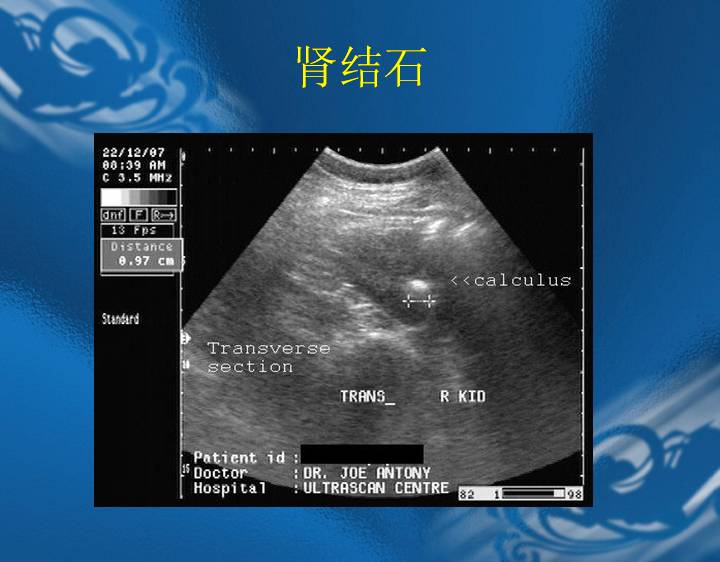

执业医师资格考试“实践技能”影像学辅导资料